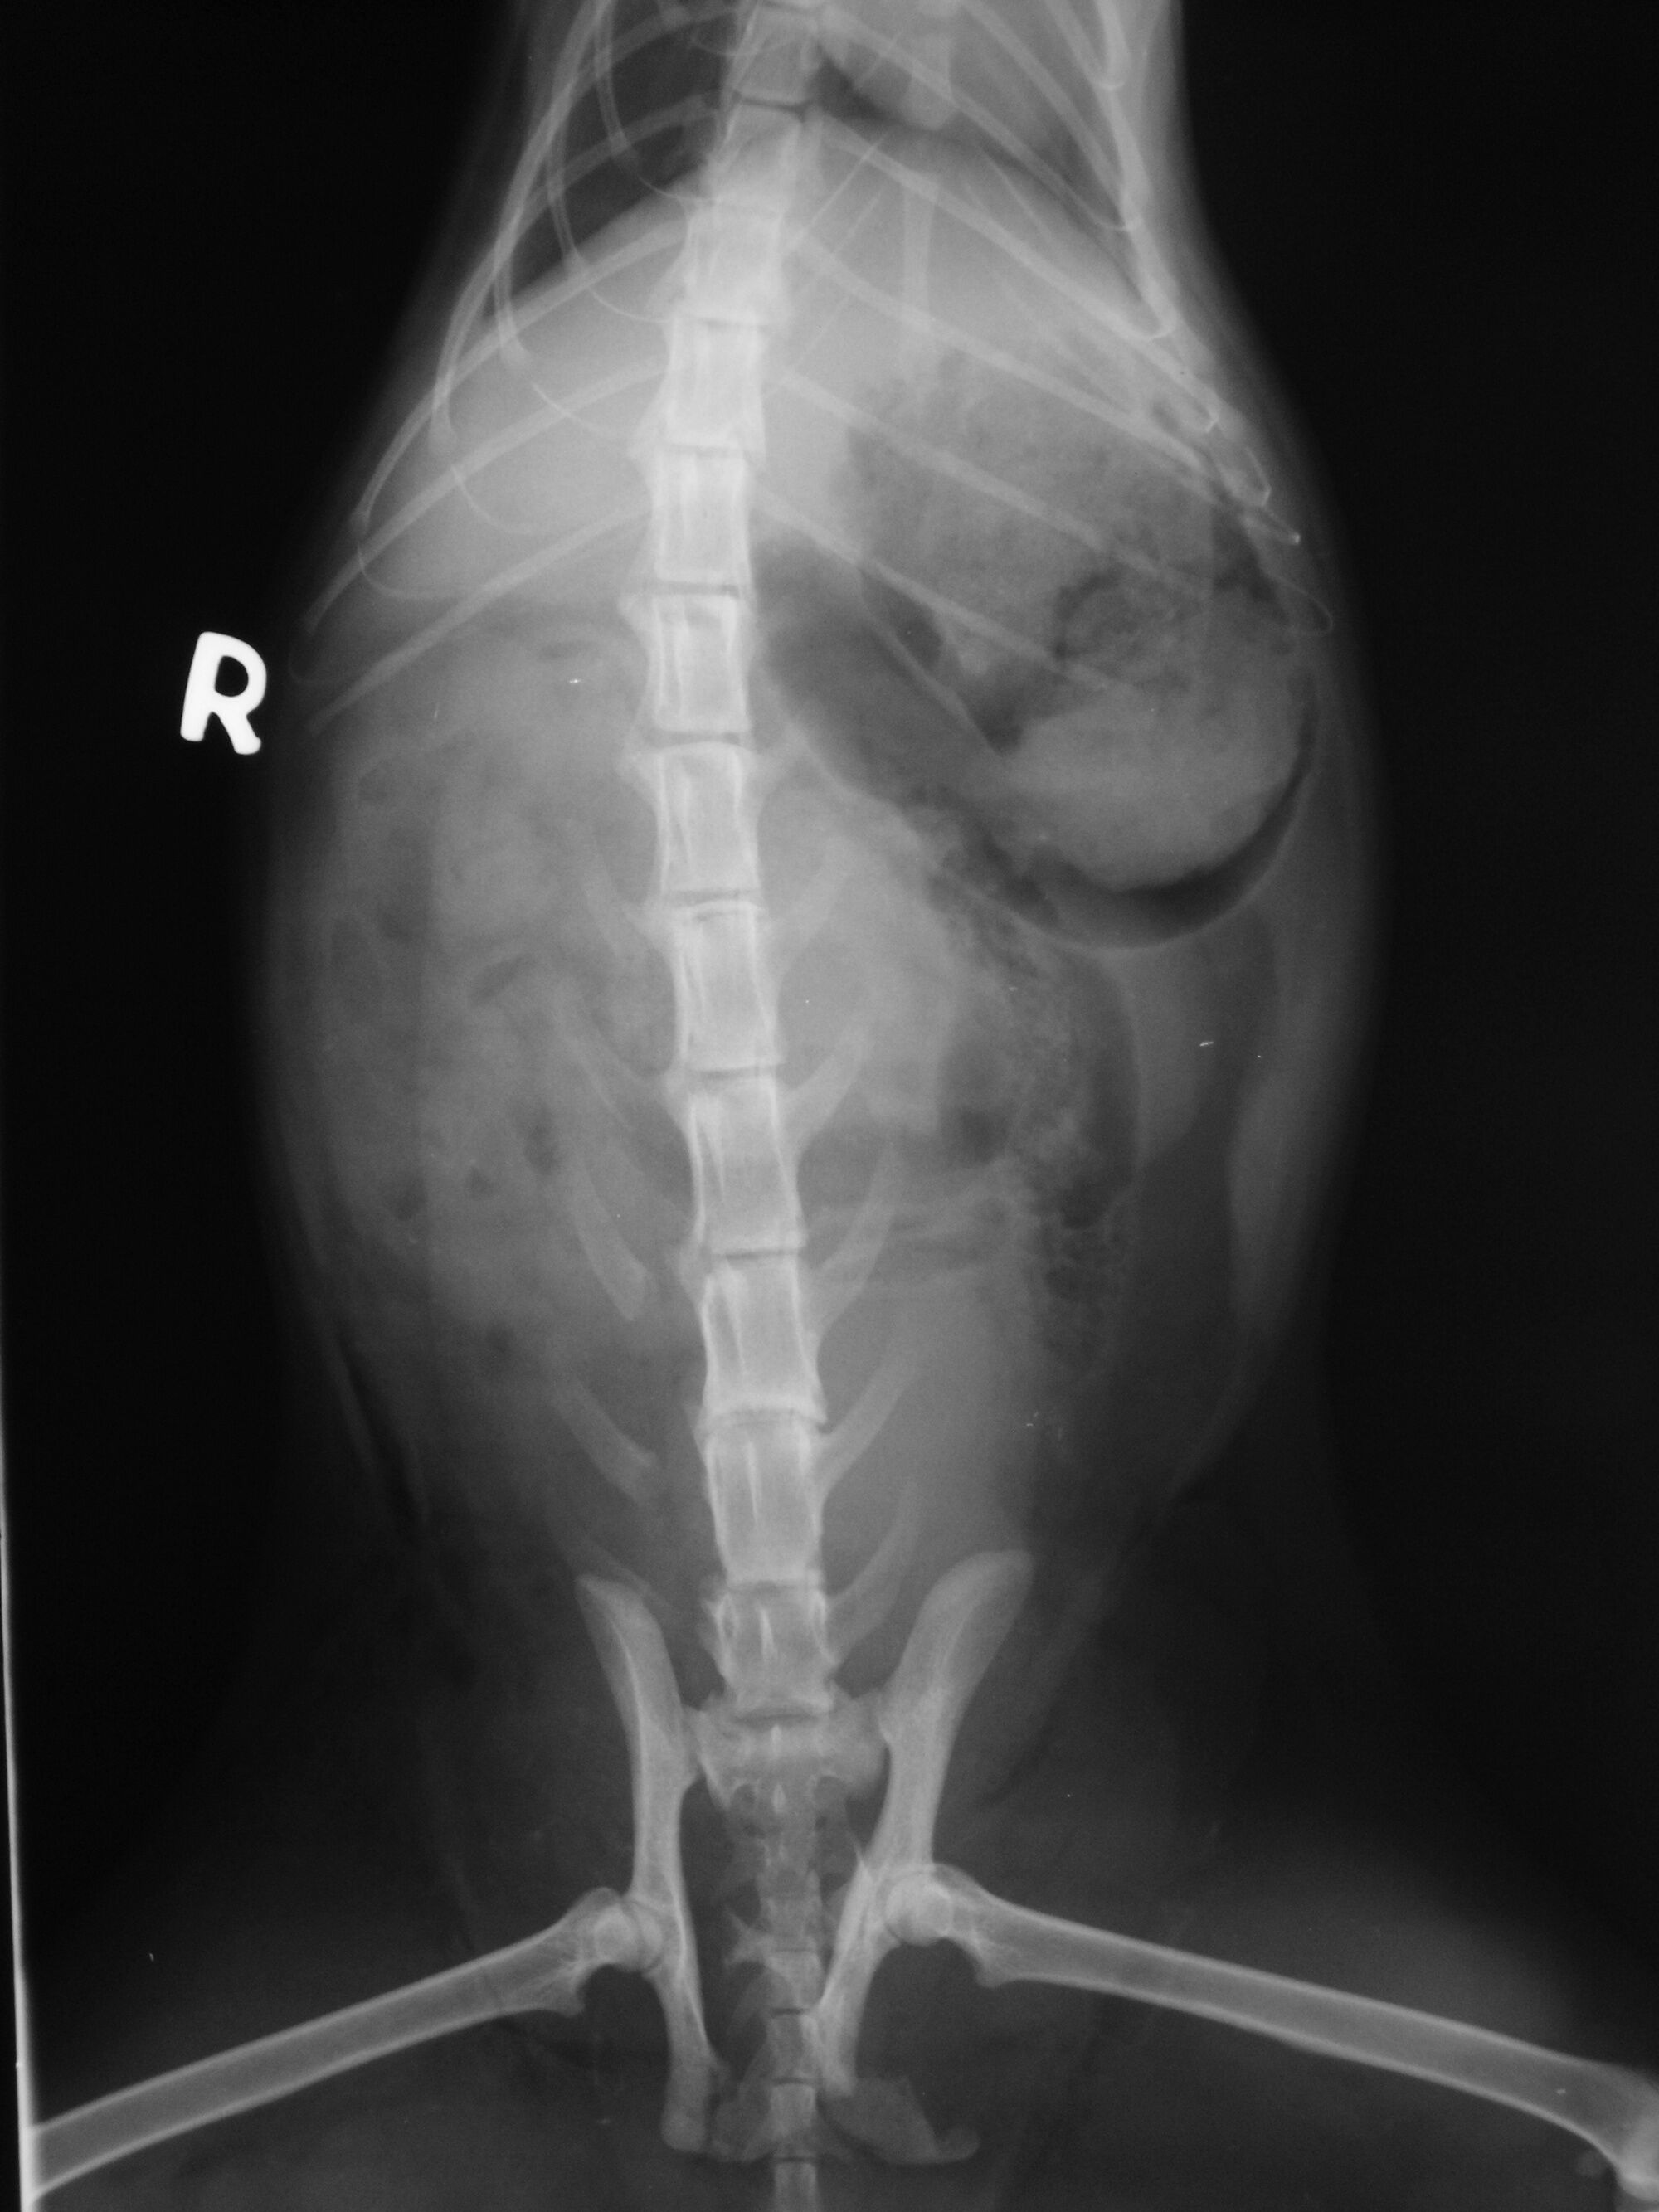

主題: 民族路被車壓過的黑貓 申請者姓名: 劉素鳳 花色: 申請日期: 2013-08-18 02:20:32 申請者部落格: 申請者臉書網址: 所在縣市/合作醫院: 高雄市/樂生動物醫院 治療費用: 3500元 需求人數: 8人 已結案 (2013-09-03 16:24:09) 報名人員: aki(已付款)、Fatefaye Wu(已付款)、楊政遠(已付款)、Wasca(已付款)、maiwu(已付款)、sally x3(已付款)、 候補人員: 動物病情說明: 這是在TNR貓途中結束後在民族路上發現的車禍貓, 當時貓躺在路邊抽動, 因為時間已經很晚緊急打電話給樂生動物醫院, 醫生將貓咪仔細檢查發現是車禍貓咪,後軀癱瘓無痛覺反應,經X光檢查,脊椎受傷(第3及第5腰椎),腸薦關節脫臼及骨盆骨折,腹部皮下氣腫及出血,點滴住院後,貓咪還是上天堂去了, 送了他一程, 感謝大家善心捐款.

6.X光檢驗 300*2=600

total 3500急救後貓後來當天使去了. 醫生發現貓是被碾過.